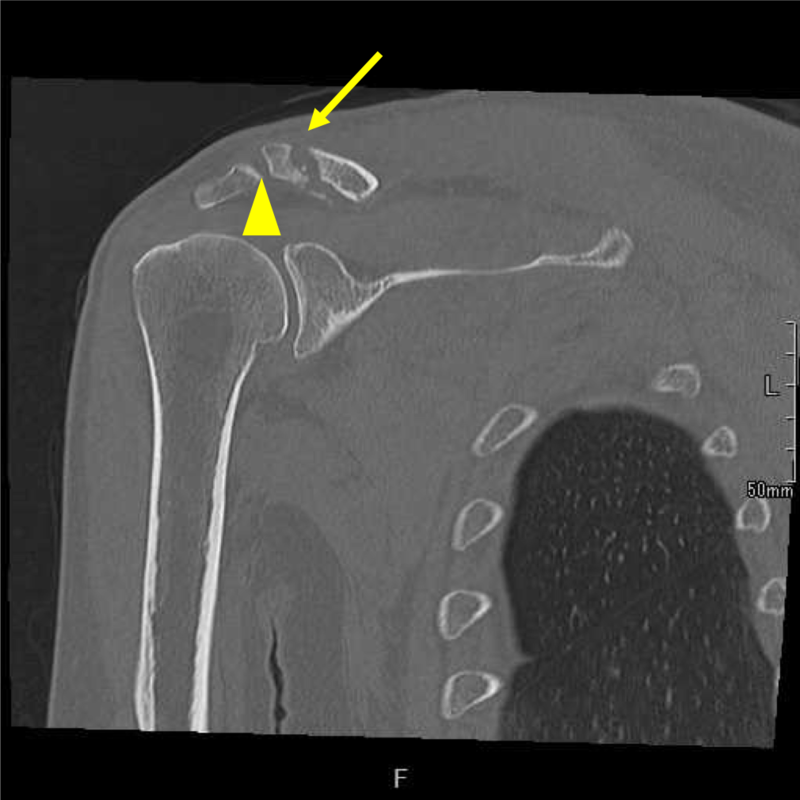

例)鎖骨遠位端骨折の偽関節

矢頭:肩鎖関節